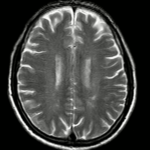

Ca lâm sàng: Ung thư đại tràng ở bệnh nhân 15 tuổi

GS.TS Mai Trọng Khoa; BSNT Hoàng Mạnh Đức, Ths Bùi Quang Lộc , PGS.TS Phạm Cẩm Phương, Bsck II Hoàng Anh, Trung tâm y học hạt nhân và...